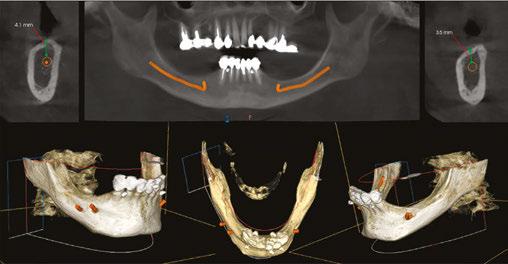

A 59-year-old male reported to the dental office with missing maxillary teeth due to poor oral hygiene. Treatment planning was done for All-on-4 implant placements followed by prosthesis. A complete medical history was obtained and was negative for any significant medical problems. The patient denied being allergic to any medication as well. The patient agreed to the implant placement and was advised to have an orthopantomogram (Figure 1).

on the crest of the ridge in the region of teeth Nos. 15-25. While creating the incision, bleeding was noticed in the region of tooth No. 15 which intensified during the flap reflection (Figure 2). Bleeding was pulsatile, indicating an arterial bleed. Initially attempts to control bleeding included a pressure pack and ice pack, and the bleeder was isolated and the vessel ligated (Figure 3). The bleeding could be controlled, and the procedure was completed by placing four Bioner implants (Bioner, Spain), size 4/10 mm. Sutures were placed, and patient was kept on basic medication for pain and infection control. Immediately after the surgery, the patient was advised to get a CBCT. As shown in Figure 4, a coronal view and Figure 4B (yellow arrows), the position of the artery can be seen.

In the follow-up sessions, the patient was comfortable, but did complain of mild swelling which subsided within 4-5 days. A post-op CBCT showed excellent recovery, bone width, and proper implant placement (Figure 5).

Figure 1: Pre-op panoramic radiograph

Figure 2 (left): Alveolar antral artery (AAA). Figure 3 (center): The artery has been ligated with suture. Figures 4A and 4B (right): CBCT post-implant placement and position of the artery coronally (top). 4B. Showing the position of alveolar antral artery (AAA) in relation to implant placement as indicated by the yellow arrows (bottom)